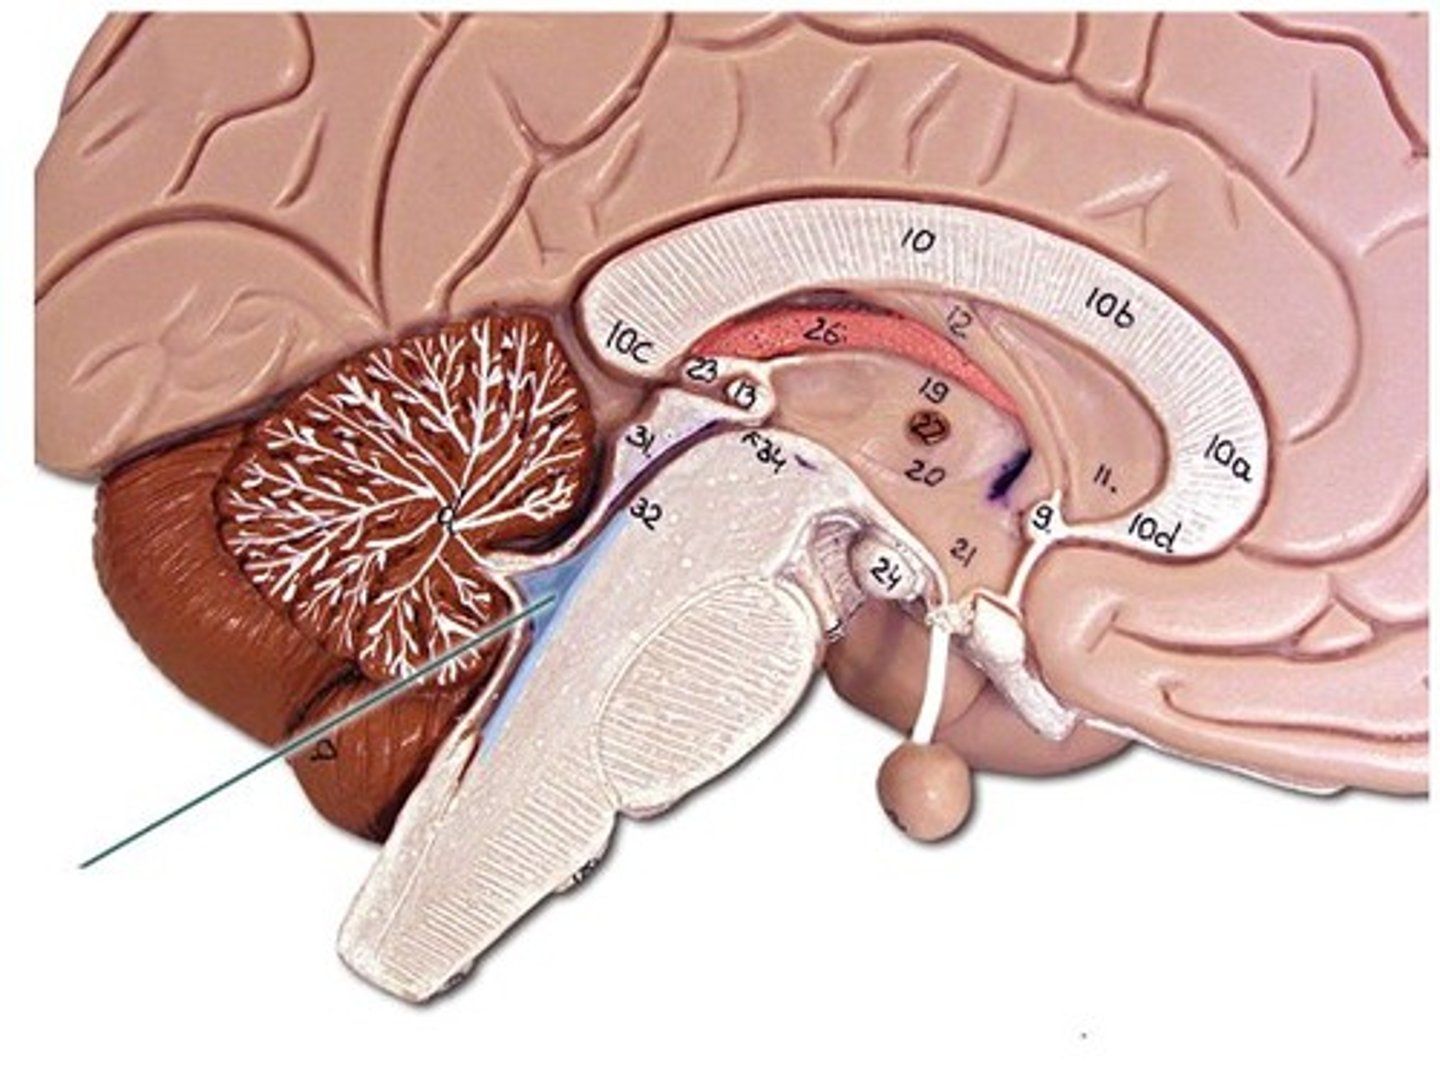

Lateral ventricles

Ventricles located in each cerebral hemisphere

Third ventricle

the ventricle located in the center of the diencephalon

Cerebral aqueduct

connects the third and fourth ventricles

Fourth ventricle

the ventricle located between the cerebellum and the dorsal pons, in the center of the metencephalon

Central canal

a fluid-filled channel in the center of the spinal cord

Inter ventricular foramen of Monroe

Passageway between lateral ventricles and third ventricle